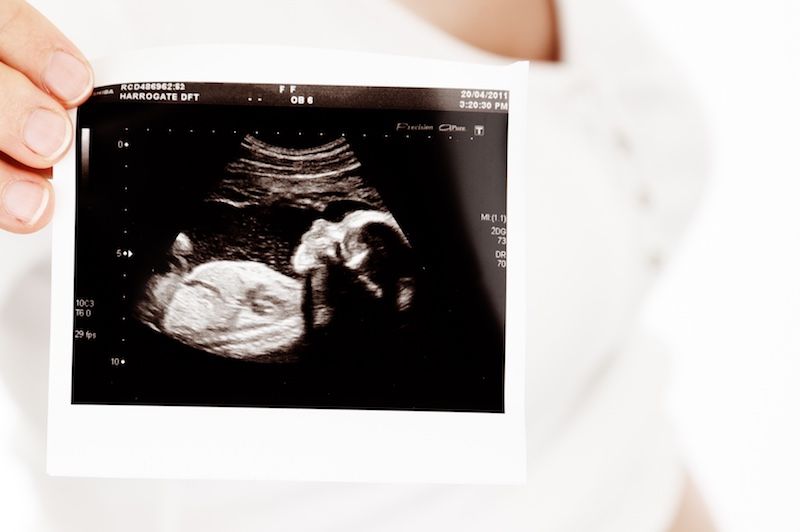

La Ecografía de Alta Resolución y Doppler son las prueba de ultrasonidos que se realizan durante el embarazo para conocer el estado del bebé y conocer si el líquido amniótico que lo envuelve es el adecuado. Estas exploraciones dentro de la obstetricia también ayudan a saber si la placenta es normal o si tiene alguna anomalía de estructura o de función.

La Ecografía Obstétrica es aquella que se realiza durante el embarazo, vía transvaginal o vía abdominal, que estudia la viabilidad de la gestación, si evoluciona según lo esperado, así como la anatomía y morfología del feto.

Esta ecografía obstétrica también informa del bienestar de su bebé dentro del útero.